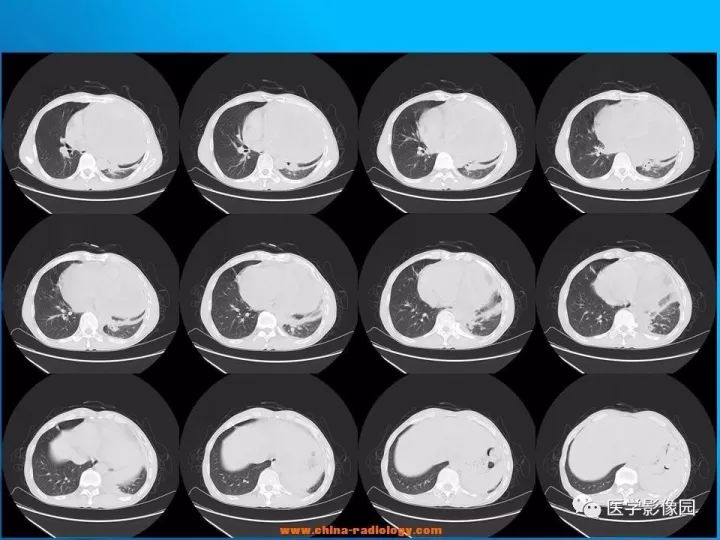

【病例】纵隔恶性神经鞘瘤1例CT

诊断结果:恶性神经鞘瘤

CT表现

1.肿瘤多为单发,平扫密度略低于肌肉,轮廓光整,呈类圆形或卵圆形,肿瘤较大时可为不规则形或呈分叶状,易囊变,常为囊实性,有包膜,可有钙化。

2.增强扫描多数病例肿瘤强化轻微,包膜可强化,少数病例可有较明显强化。

3.当肿块体积较大,并向周围侵犯,其内密度混杂,尤其是囊变、坏死明显;实性部分呈斑片状及网格状较明显强化;往往提示为恶性神经鞘瘤。